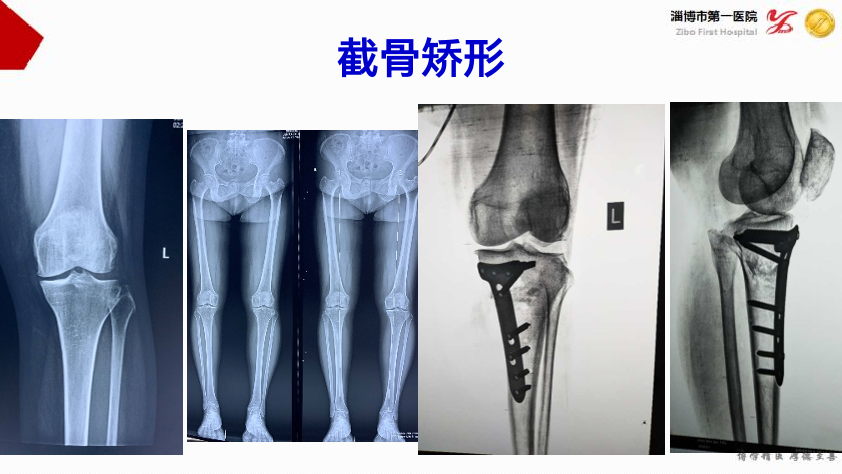

膝关节炎